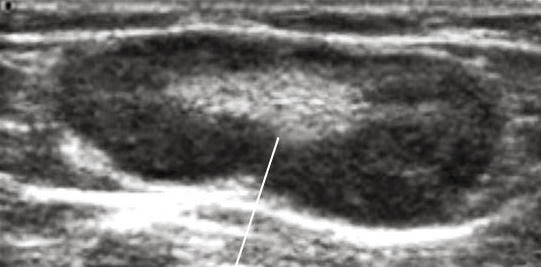

Лимфома На Узи Фото